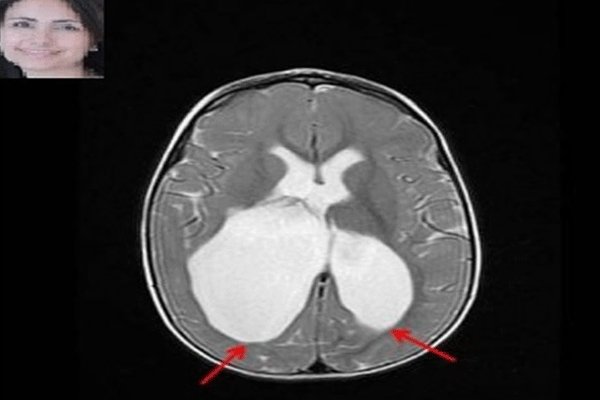

فلج مغزی به مجموعه ای از علائم عصبی اطلاق می شود که به اختلال در حرکت و وضعیت کودک منجر می شود. مطالعات اخیر نقش پایه ای ژنتیک را در بروز فلج مغزی ثابت کرده و مانند بیشتر بیماری های نوروژنتیک، نحوه وراثت چند عاملی (مولتی فاکتوریال) برای آن مطرح شده است.

محققان در مطالعات گذشته چندین عامل خطرساز مرتبط با بارداری از جمله زایمان زودرس، رشد غیر طبیعی، قرار گرفتن در معرض عفونت و کمبود اکسیژن در هنگام تولد را شناسایی کرده بودند. فلج مغزی، در توانایی حرکت کردن اعضای بدن و حفظ تعادل اثر می گذارد.